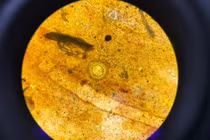

| Sán xuất hiện khắp cơ thể người bệnh. Ảnh: BVCC |